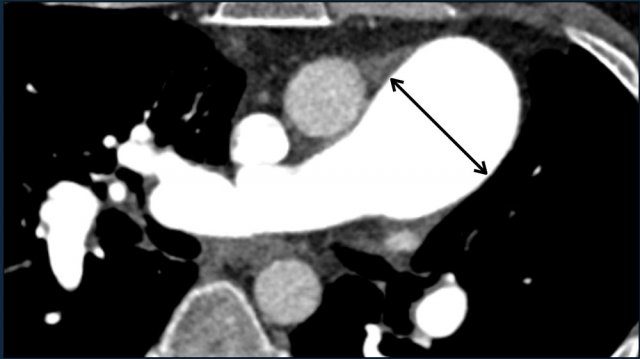

Cardiovascular Pearls on Chest CT...